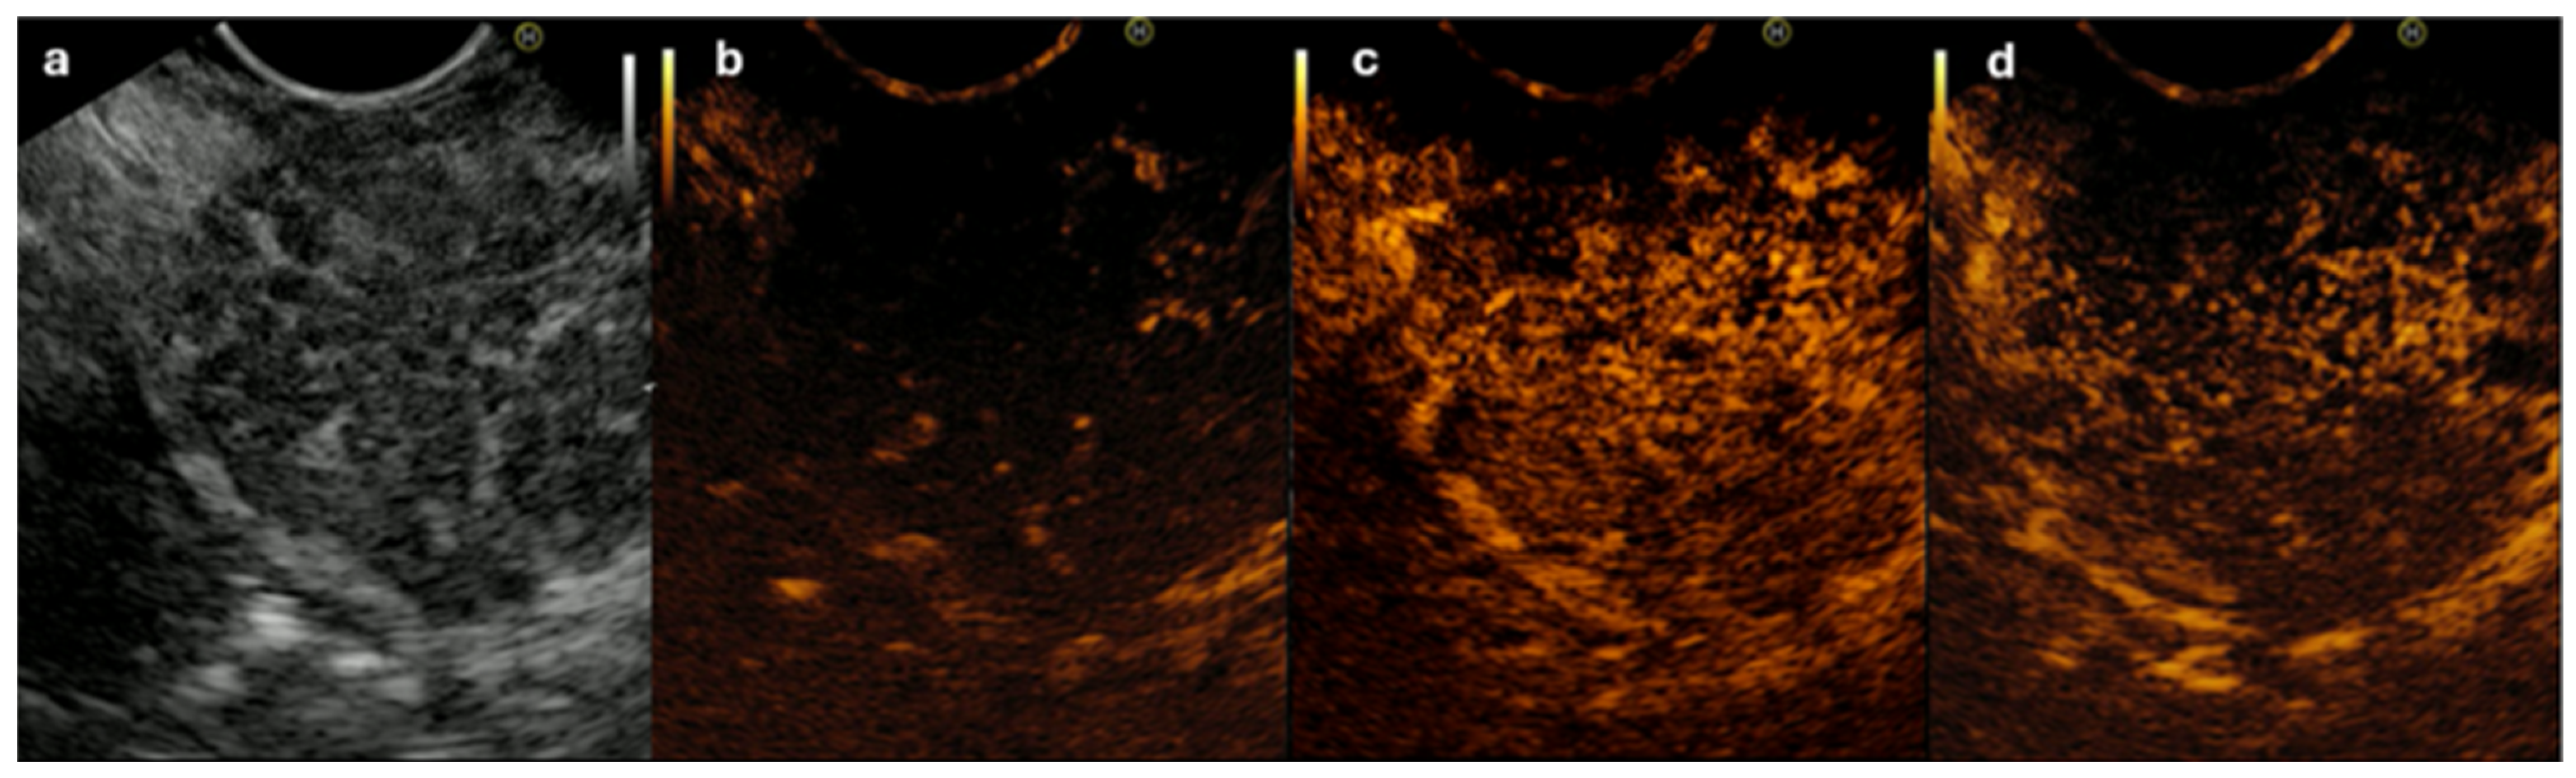

- Imazu, H.; Kanazawa, K.; Mori, N.; Ikeda, K.; Kakutani, H.; Sumiyama, K.; Hino, S.; Ang, T.L.; Omar, S.; Tajiri, H. Novel quantitative perfusion analysis with contrast-enhanced harmonic EUS for differentiation of autoimmune pancreatitis from pancreatic carcinoma. Scand. J. Gastroenterol. 2012, 47, 853–860. [Google Scholar] [CrossRef] [PubMed]

- Cho, M.K.; Moon, S.-H.; Song, T.J.; Kim, R.E.; Oh, D.W.; Park, D.H.; Lee, S.S.; Seo, D.W.; Lee, S.K.; Kim, M.-H. Contrast-Enhanced Endoscopic Ultrasound for Differentially Diagnosing Autoimmune Pancreatitis and Pancreatic Cancer. Gut Liver 2018, 12, 591–596. [Google Scholar] [CrossRef] [PubMed]

- Buxbaum, J.; Ko, C.; Varghese, N.; Lee, A.; Sahakian, A.; King, K.; Serna, J.; Lee, H.; Tchelepi, H.; Van Dam, J.; et al. Qualitative and Quantitative Contrast-enhanced Endoscopic Ultrasound Improves Evaluation of Focal Pancreatic Lesions. Clin. Gastroenterol. Hepatol. 2020, 18, 917–925.e4. [Google Scholar] [CrossRef] [PubMed]

- Săftoiu, A.; Vilmann, P.; Dietrich, C.F.; Iglesias-Garcia, J.; Hocke, M.; Seicean, A.; Ignee, A.; Hassan, H.; Streba, C.T.; Ioncică, A.M.; et al. Quantitative contrast-enhanced harmonic EUS in differential diagnosis of focal pancreatic masses (with videos). Gastrointest. Endosc. 2015, 82, 59–69. [Google Scholar] [CrossRef]

- Ishikawa, T.; Hirooka, Y.; Kawashima, H.; Ohno, E.; Hashizume, K.; Funasaka, K.; Nakamura, M.; Miyahara, R.; Watanabe, O.; Ishigami, M.; et al. Multiphase evaluation of contrast-enhanced endoscopic ultrasonography in the diagnosis of pancreatic solid lesions. Pancreatology 2018, 18, 291–297. [Google Scholar] [CrossRef] [PubMed]

| Contrast-enhanced EUS | Hyper-isoenhancement Homogeneous contrast agent distribution Absent irregular internal vessels [80] | Iso-hypoenhancement Arterial irregularity and absent venous vasculature [80] |